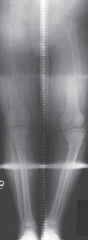

Chapter 35 Guided Growth to Correct Limb Deformity Peter M. Stevens DEFINITION Physiologic genu varum (before…

Chapter 30 Surgical Management of Blount’s Disease Eric D. Shirley and Richard S. Davidson DEFINITION Blount’…